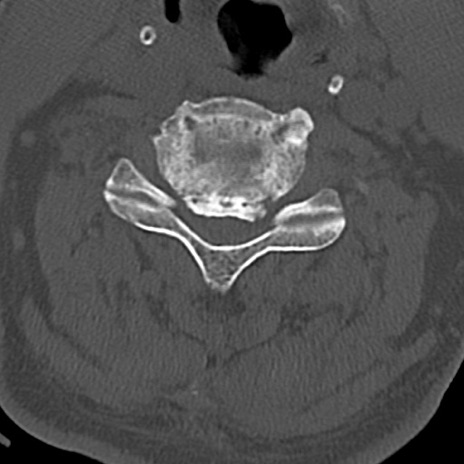

頚椎CT

横断像